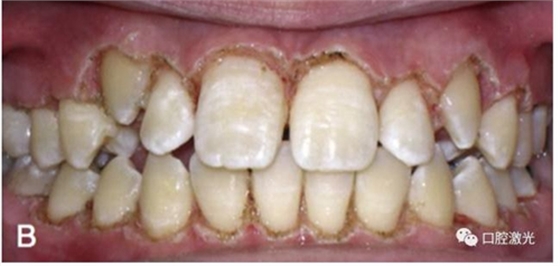

有時,會遇到一些口腔衛(wèi)生問題比較嚴重的患者,從而導(dǎo)致牙齦發(fā)炎而腫大。通過改善口腔衛(wèi)生環(huán)境,炎癥可以得到緩解,但增生的牙齦不一定都可以完全恢復(fù)。下圖的患者就存在口腔牙齦肥厚問題,同時左上部犬牙存在部分萌出的問題,右上部犬牙存在未萌出問題,這些問題都妨礙了托槽的粘接。因此,實施了全口腔的牙齦整形手術(shù)。去除了多余的牙齦組織,增加了犬牙的暴露面積,從而使托槽的粘接更為便利,同時也提升了患者保持口腔衛(wèi)生的狀況。

治療前